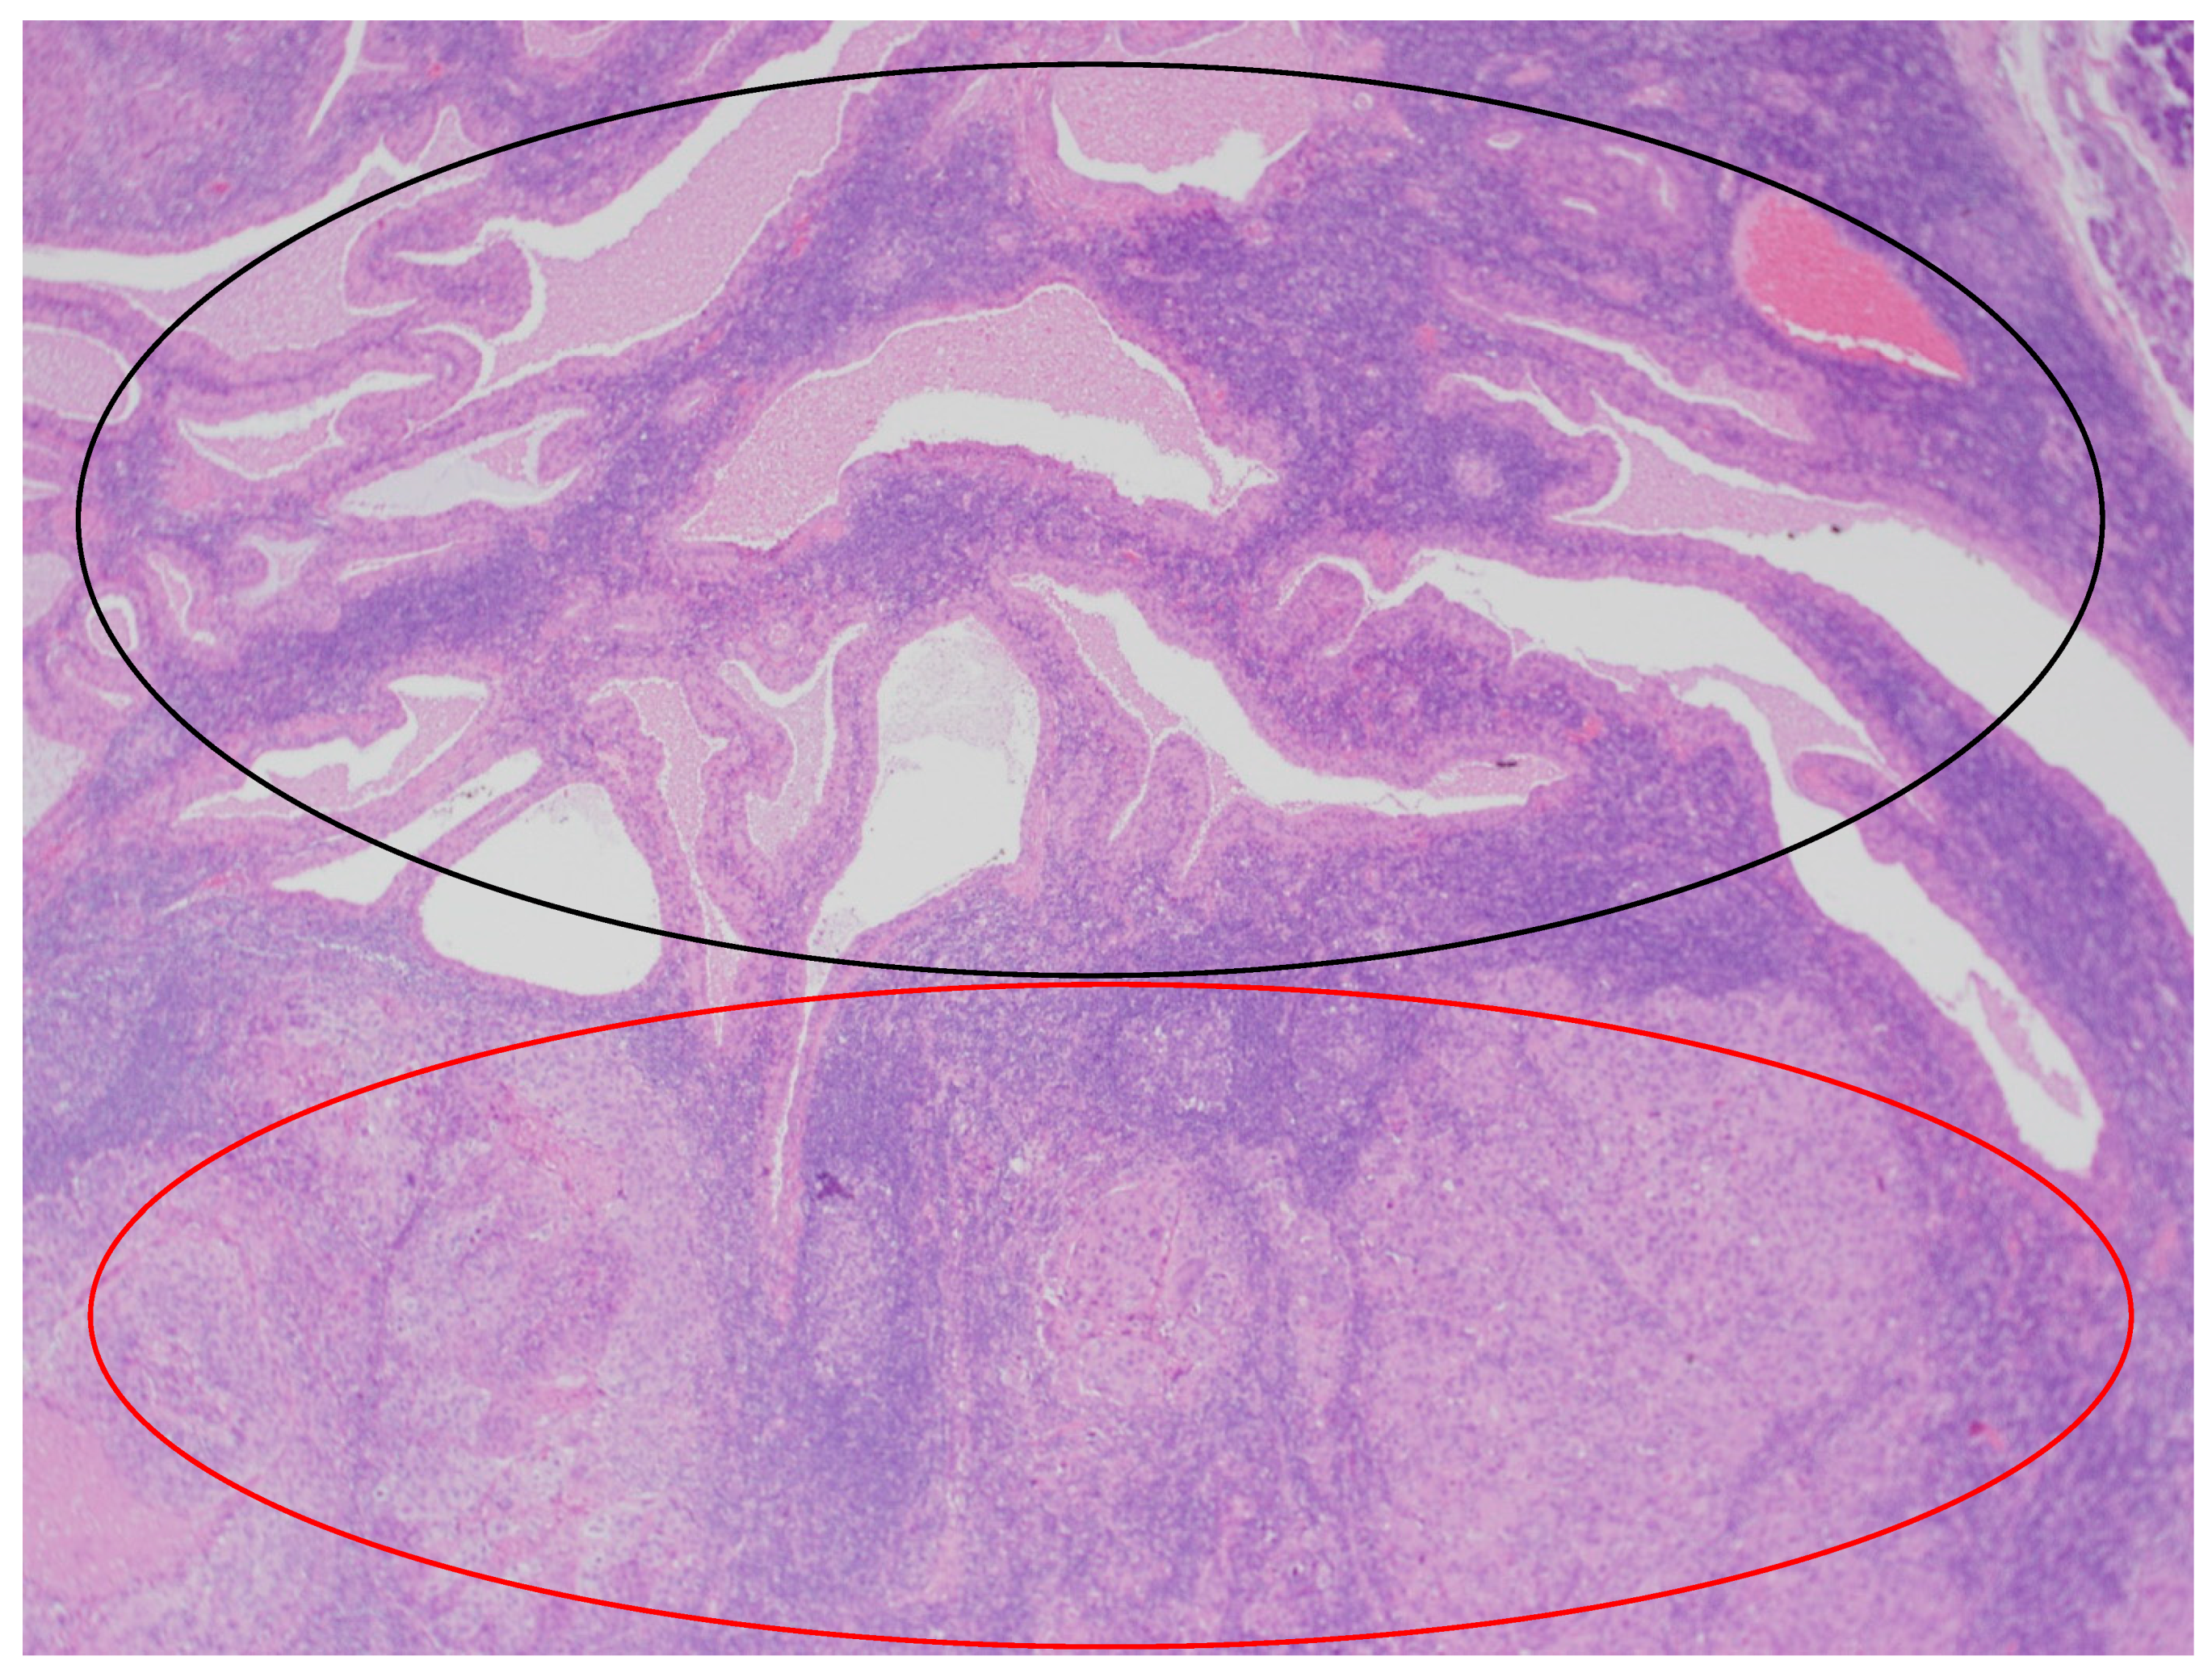

In the histopathological examination of the remaining components of the surgical specimen, a parotid Warthin tumor was found; in the majority, it was occupied and destroyed by the metastatic squamous carcinoma (with the largest metastasis dimension of about 24 mm) (Figure 3, Figure 4 and Figure 5) and radically removed. A second small parotid Warthin tumor, not involved in the cancer metastasis, was removed nearby. Additionally, a cancer metastasis 10.7 mm in diameter in the intraparotid lymph node and a small lymph node with cancer metastasis 1.4 mm in diameter were found, without extranodal extension (ENE-), and were also completely removed. The examination of 12 lymph nodes in the neck specimen did not reveal metastases; thus, the final pathological stage established, according to the 2017 AJCC classification, was pT3N2b (ENE-) with LVI2, PNI0, and R0.

Figure 3.

The parotid Warthin tumor, with the benign epithelial cystic component in the superior part of the photo (black circle) and squamous cell carcinoma metastasis in the inferior part (red circle). HE staining. Magn. ×88.